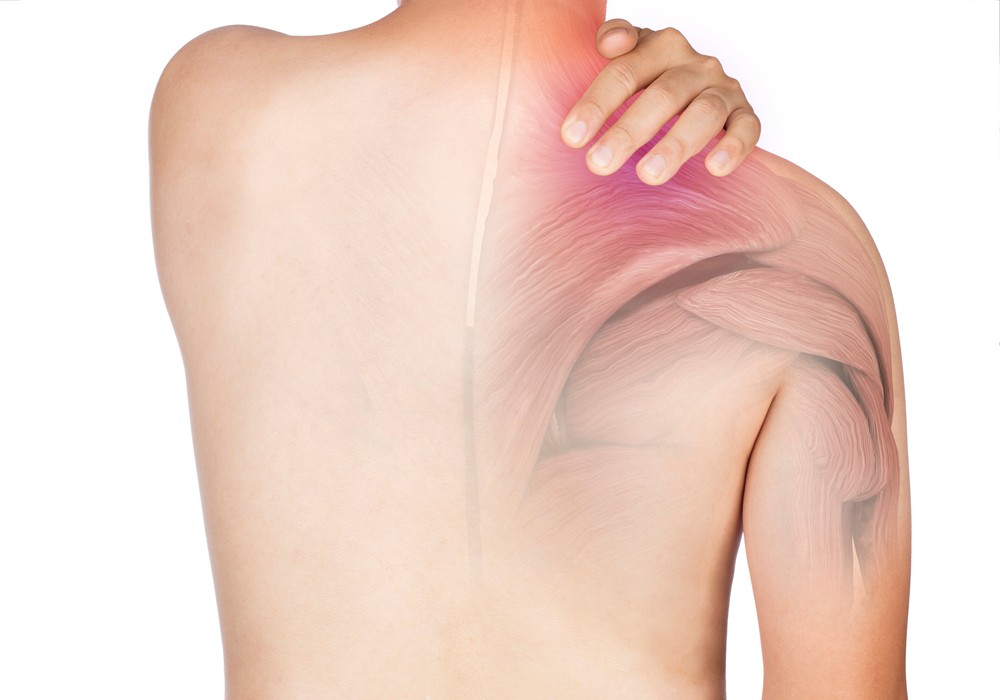

Показания к рентгену лопатки

Ситуации, когда требуется рентген лопатки:

- постоянная или временная боль, дискомфорт в лопатке неясного происхождения;

- болезненность в плечевом суставе;

- отек тканей лопатки, видимая гиперемия;